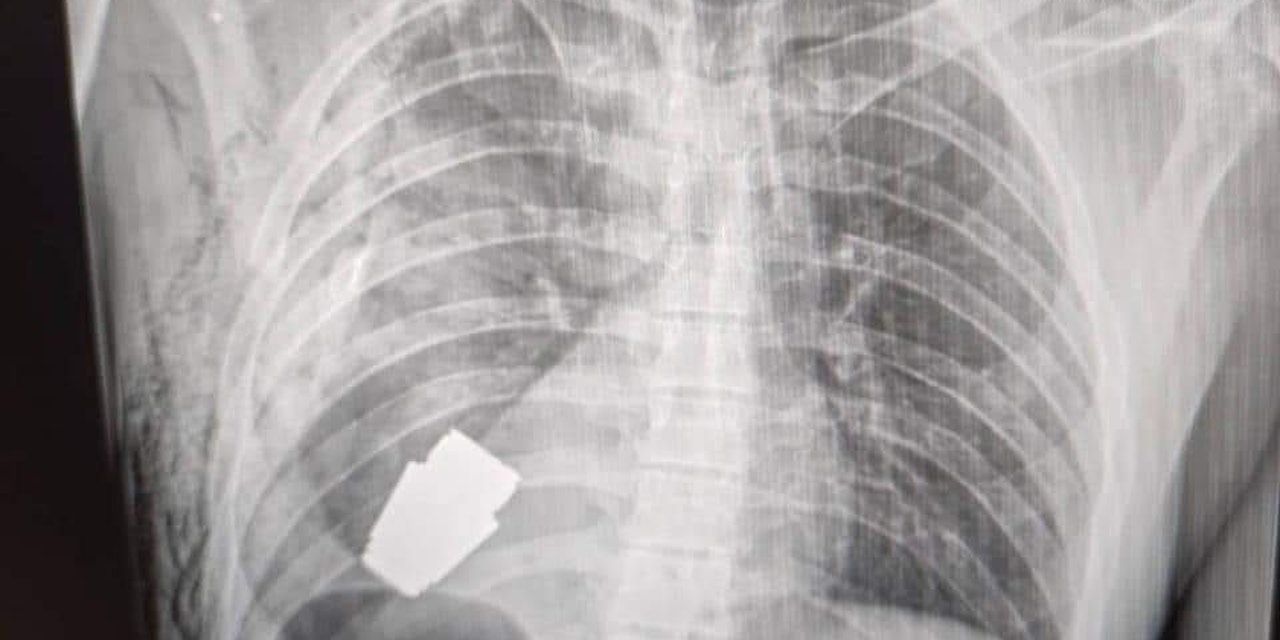

Die Geschichte medizinischer Ausnahmeoperationen ist um ein Kapitel reicher: Ein erfahrener Militärchirurg brachte es fertig, einem verwundeten ukrainischen Soldaten eine Granate aus dem Brustkorb zu holen, die jederzeit hätte explodieren können.

Beim Geschoss soll es sich um eine sogenannte VOG-Granate gehandelt haben, die aus tragbaren russischen Granatwerfern verschossen werden. Meist sind die Projektile mit Streugeschossen gefüllt, die bei der Detonation alles um sie herum zerfetzen.